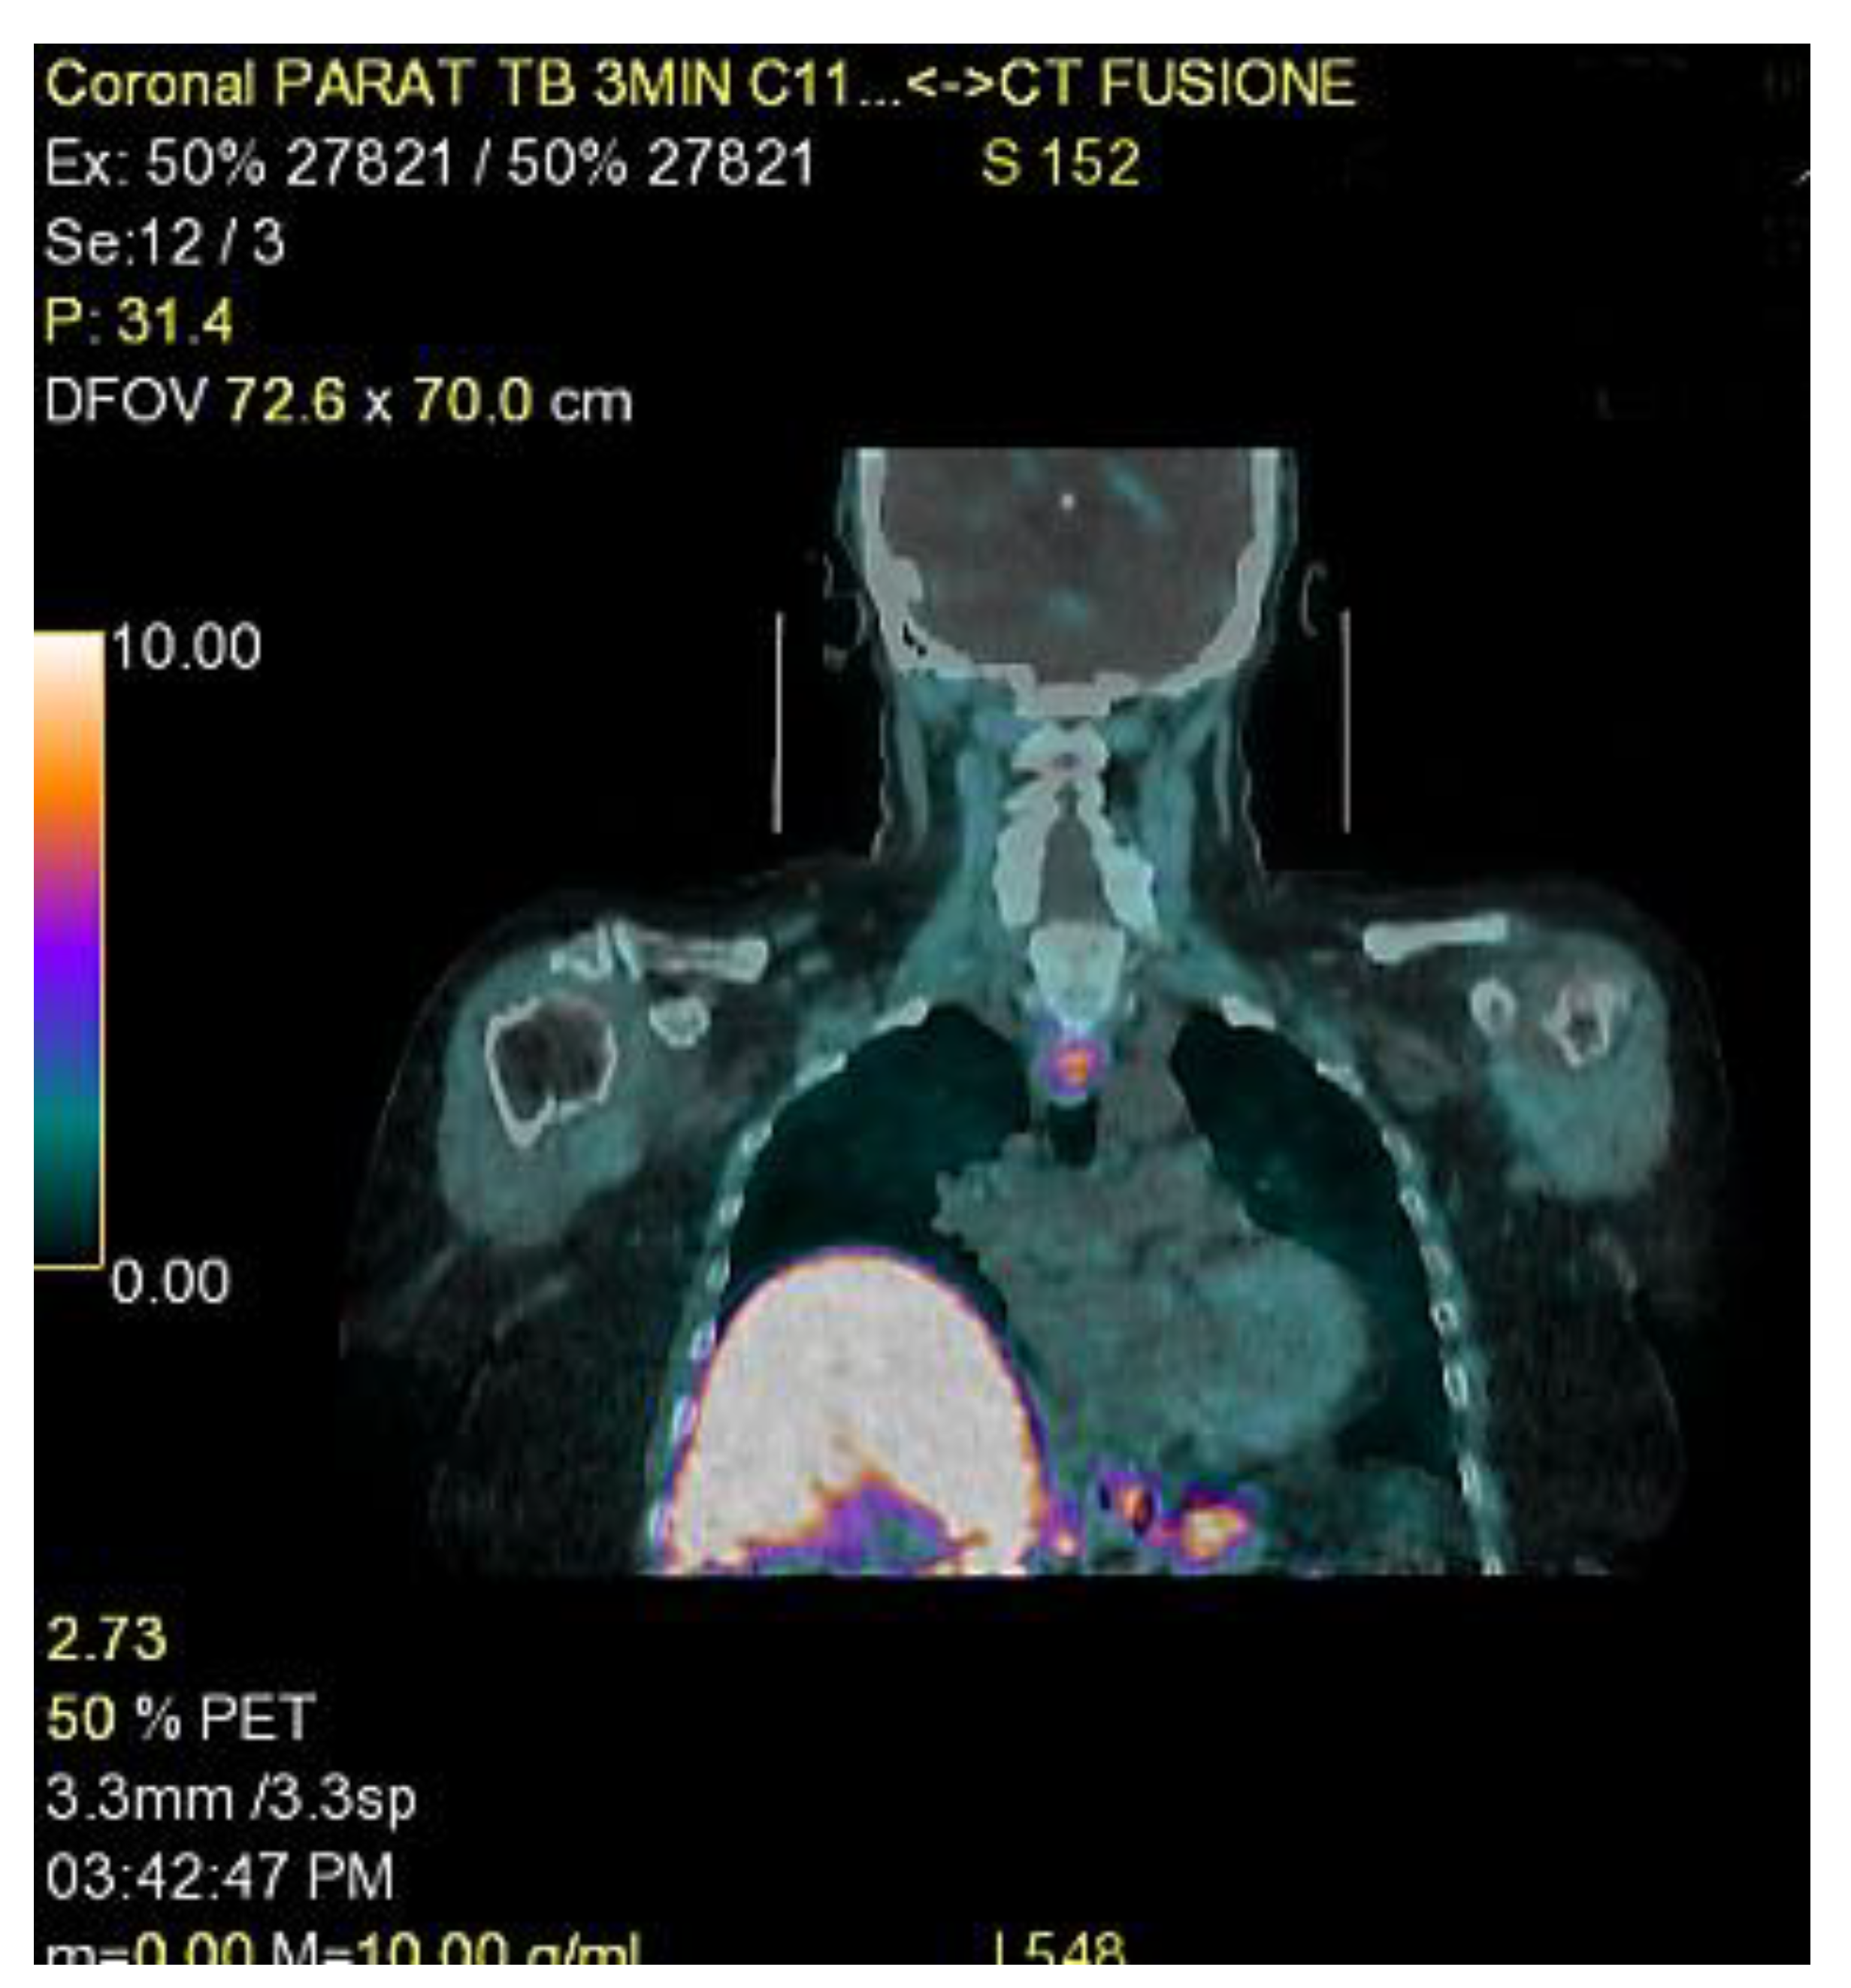

- Petranović Ovčariček, P.; Giovanella, L.; Carrió Gasset, I.; Hindié, E.; Huellner, M.W.; Luster, M.; Piccardo, A.; Weber, T.; Talbot, J.N.; Verburg, F.A. The EANM practice guidelines for parathyroid imaging. Eur. J. Nucl. Med. Mol. Imaging 2021, 48, 2801–2822. [Google Scholar] [CrossRef]

- Boudousq, V.; Guignard, N.; Gilly, O.; Chambert, B.; Mamou, A.; Moranne, O.; Zemmour, M.; Sharara, H.; Lallemant, B. Diagnostic Performance of Cervical Ultrasound, 99mTc-Sestamibi Scintigraphy, and Contrast-Enhanced 18F-Fluorocholine PET in Primary Hyperparathyroidism. J. Nucl. Med. 2022, 63, 1081–1086. [Google Scholar] [CrossRef]

- Evangelista, L.; Ravelli, I.; Magnani, F.; Iacobone, M.; Giraudo, C.; Camozzi, V.; Spimpolo, A.; Cecchin, D. 18F-choline PET/CT and PET/MRI in primary and recurrent hyperparathyroidism: A systematic review of the literature. Ann. Nucl. Med. 2020, 34, 601–619. [Google Scholar] [CrossRef]

- Michaud, L.; Balogova, S.; Burgess, A.; Ohnona, J.; Huchet, V.; Kerrou, K.; Lefèvre, M.; Tassart, M.; Montravers, F.; Périé, S.; et al. A pilot comparison of 18F-fluorocholine PET/CT, ultrasonography and 123I/99mTc-sestaMIBI dual-phase dual-isotope scintigraphy in the preoperative localization of hyperfunctioning parathyroid glands in primary or secondary hyperparathyroidism: Influence of thyroid anomalies. Medicine 2015, 94, e1701. [Google Scholar]

- Cuderman, A.; Senica, K.; Rep, S.; Hocevar, M.; Kocjan, T.; Sever, M.J.; Zaletel, K.; Lezaic, L. 18F-Fluorocholine PET/CT in Primary Hyperparathyroidism: Superior Diagnostic Performance to Conventional Scintigraphic Imaging for Localization of Hyperfunctioning Parathyroid Glands. J. Nucl. Med. 2020, 61, 577–583. [Google Scholar] [CrossRef]